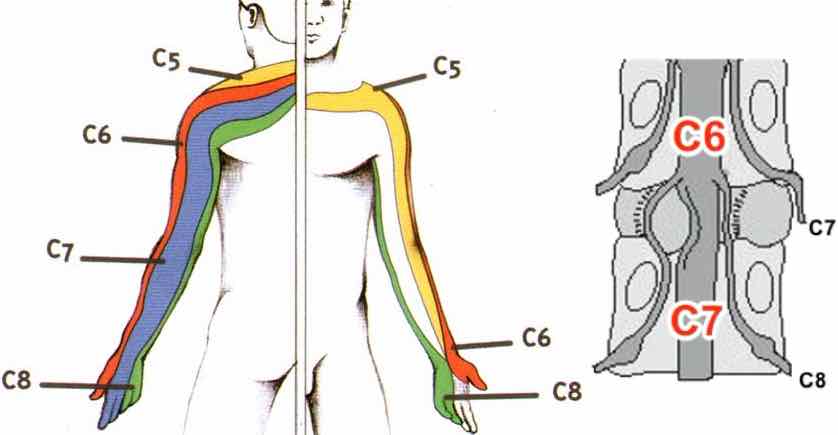

Absence d’anomalie de la charnière cervico-occipitale.

Lordose physiologique et bon alignement des corps vertébraux.

Rapports articulaires, hauteurs somatiques et espaces intersomatiques respectés.

Absence de rétrécissement significatif du canal vertébral ou des foramina.

Absence de lésion osseuse post-traumatique ou suspecte.

Parties molles paravertébrales sans particularité.

Séquences sagittales T1 et T2 STIR, ainsi que 3D T2.

Lordose physiologique du rachis cervical conservée.

Hauteurs somatiques et rapports articulaires conservés.

Absence d’anomalie de la charnière cervico-occipitale.

Absence de discopathie significative.

Pas d'étroitesse constitutionnelle du canal rachidien.

Absence d’anomalie du signal du cordon médullaire ou du LCR.

Parties molles notamment pré-vertébrales sans particularité.